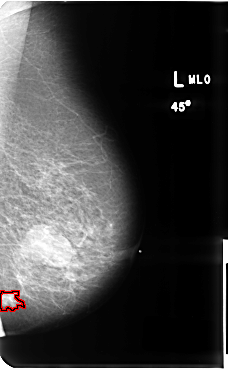

B_3512_1.LEFT_MLO

LEFT_MLO LINES 4800 PIXELS_PER_LINE 2960 BITS_PER_PIXEL 12 RESOLUTION 50 OVERLAY

FILE: B_3512_1.LEFT_MLO.OVERLAY

TOTAL_ABNORMALITIES 1

ABNORMALITY 1

LESION_TYPE CALCIFICATION TYPE PLEOMORPHIC DISTRIBUTION CLUSTERED

LESION_TYPE MASS SHAPE IRREGULAR-ARCHITECTURAL_DISTORTION MARGINS SPICULATED

ASSESSMENT 5

SUBTLETY 4

PATHOLOGY MALIGNANT

TOTAL_OUTLINES 1

BOUNDARY